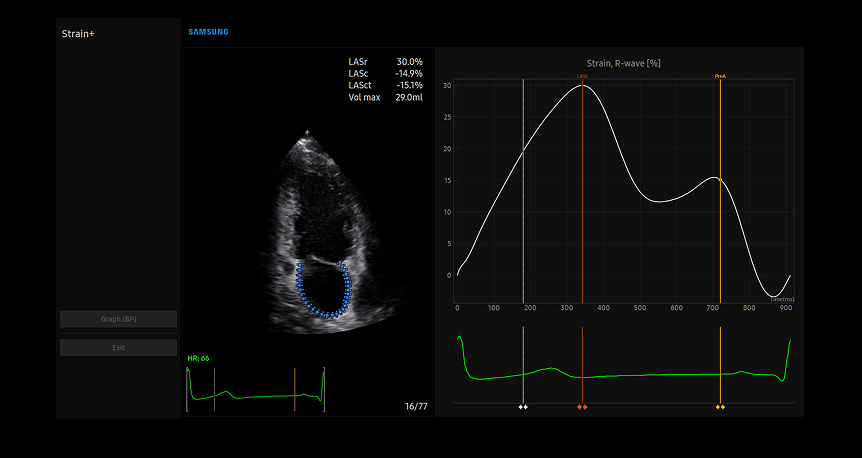

Strain+1 LA

Left atrial strain assessment technology with blue-tracked myocardial movement and corresponding strain curve graph for specialized cardiac function evaluation

Strain+ è uno strumento quantitativo per misurare il movimento della parete globale e segmentale del ventricolo sinistro (LV), dell'atrio sinistro (LA), di e del ventricolo destro (RV) per la funzione sistolica e diastolica del cuore.